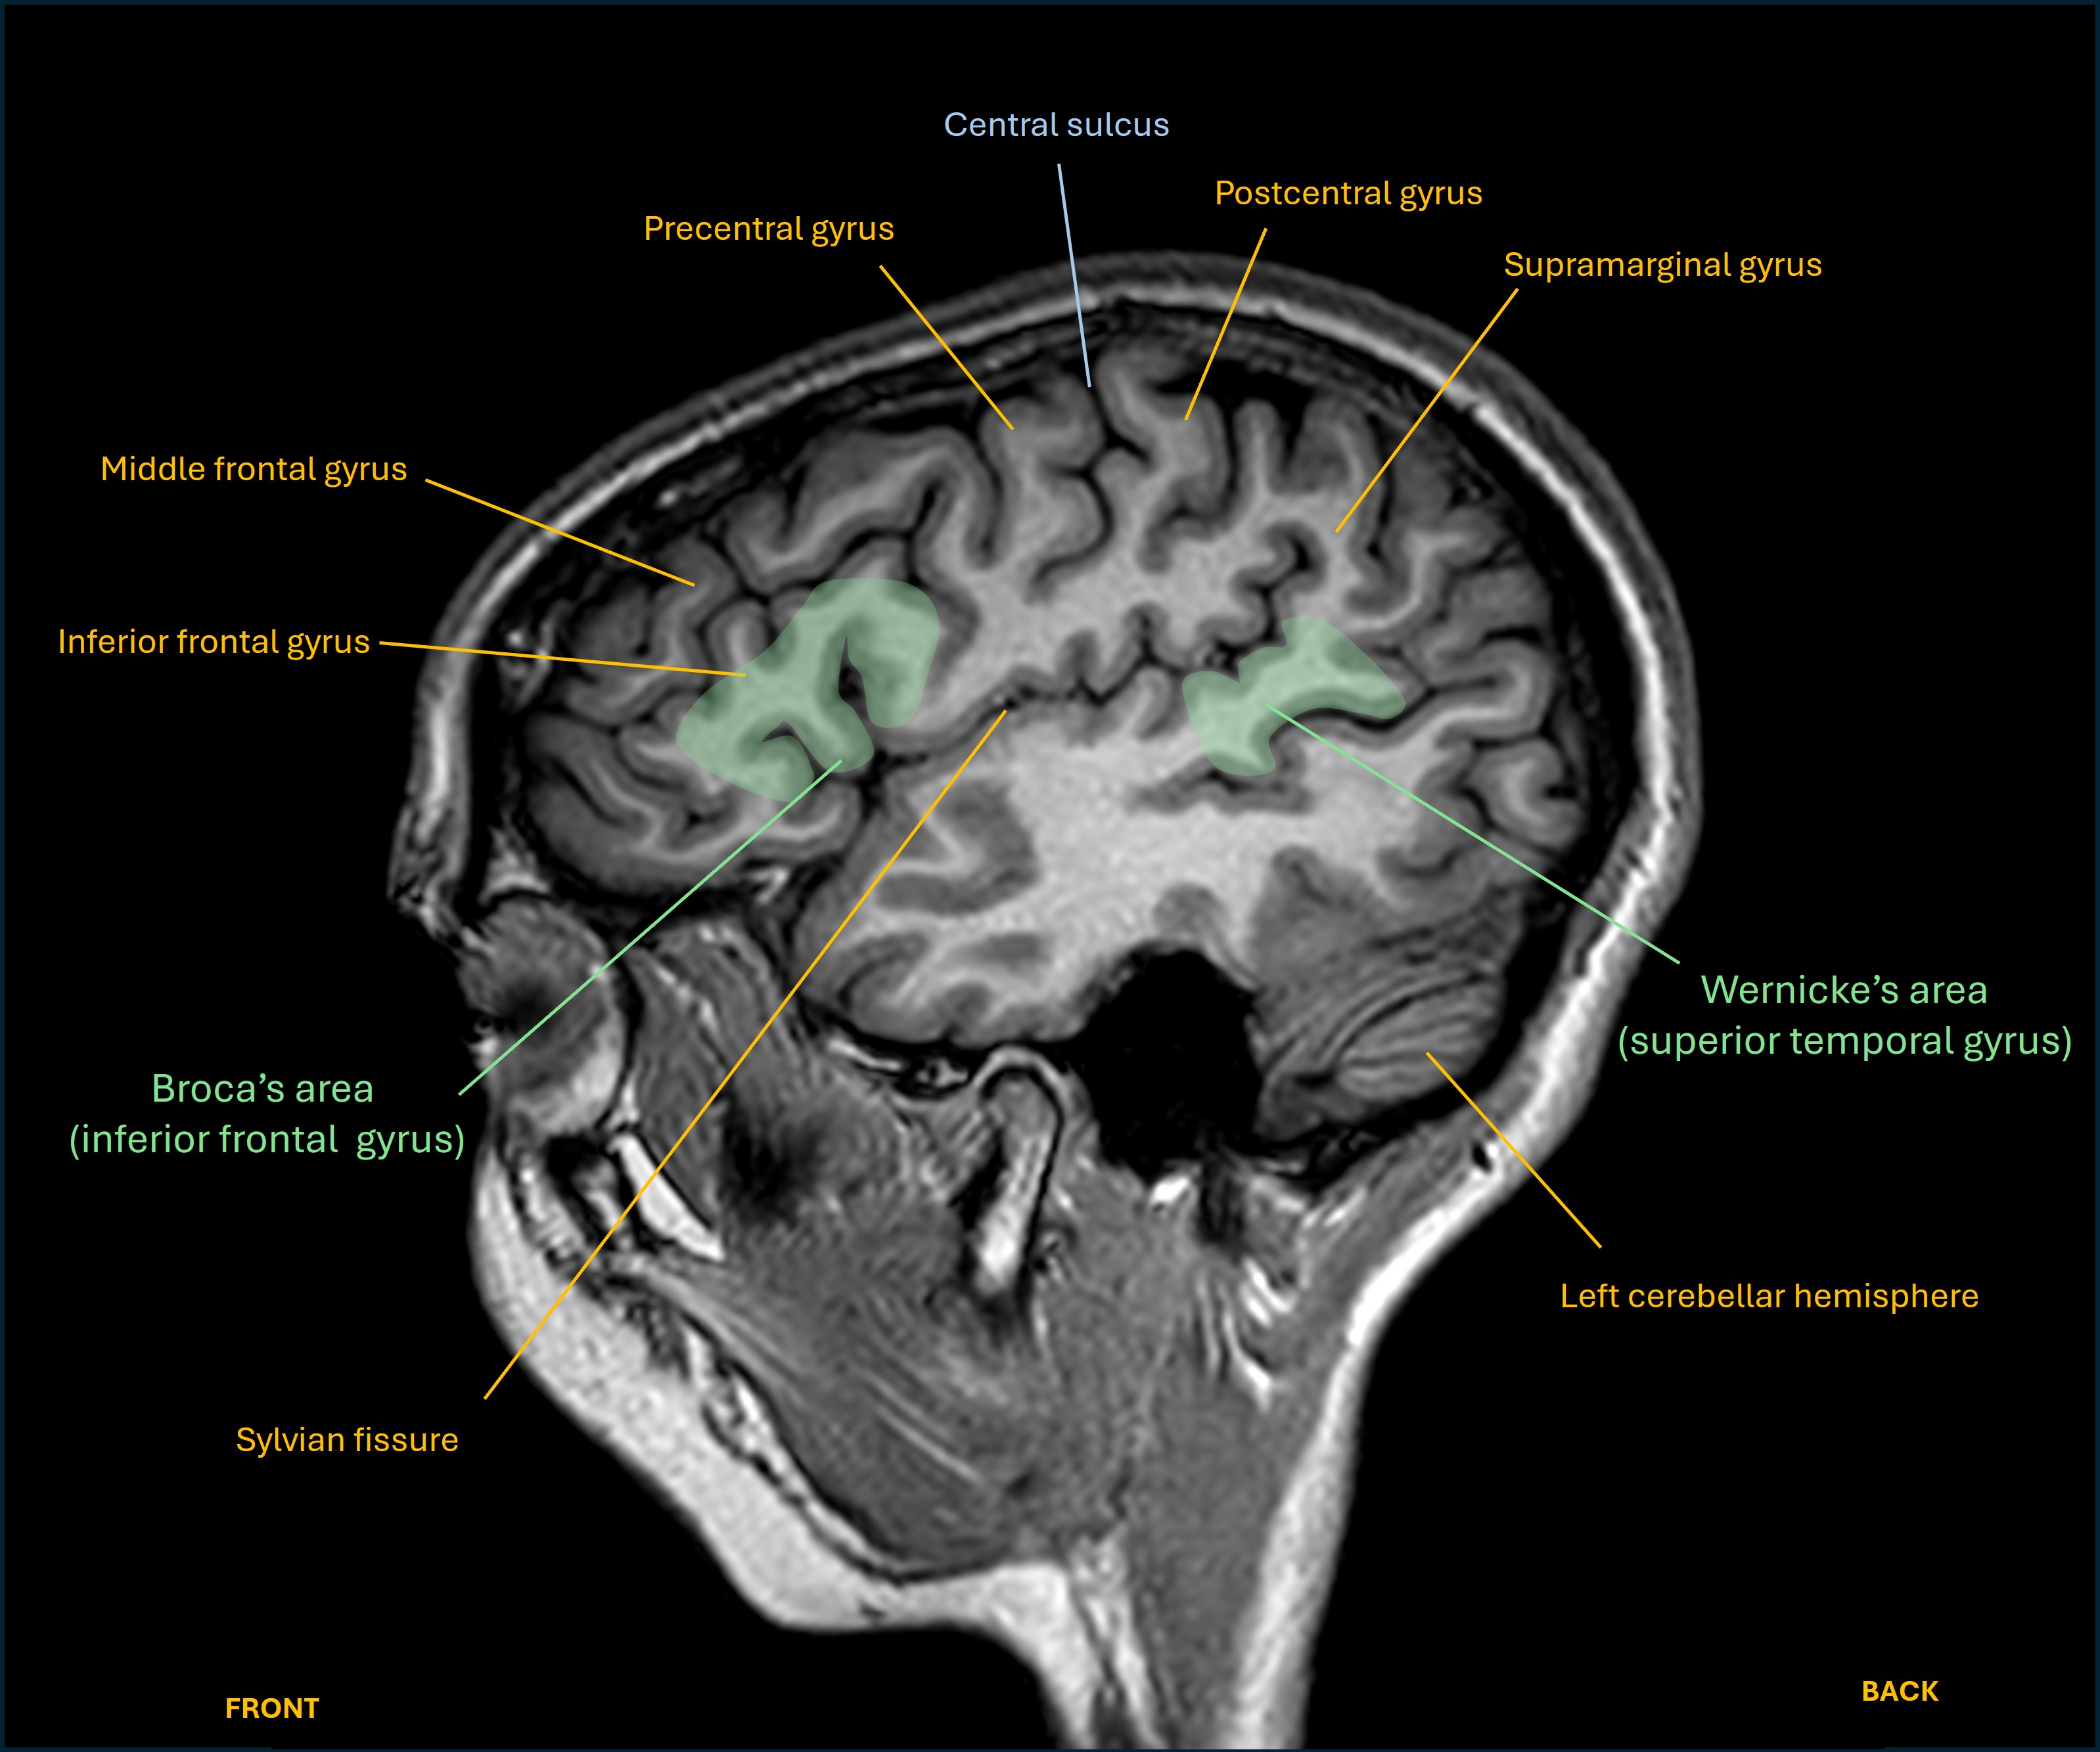

The expressive part relies on a frontal lobe area in the inferior frontal gyrus, known as Broca's area. On lateral views of the brain it looks like an M-shaped gyrus above the anterior part of the Sylvian fissure.

The receptive part is centred in the posterior part of the superior temporal gyrus, known as Wernicke's area. It's at the rear end of the Sylvian fissure, where the temporal lobe and parietal lobe meet.

Axial and sagittal views are shown below on T1 MRI, as well as a close up of the M-shaped region and its three components.

Sagittal language